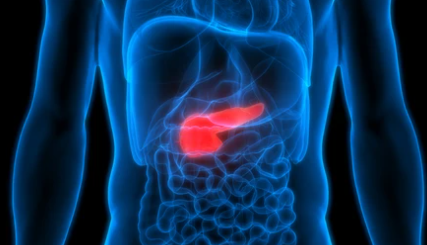

간암 말기 증상

간암말기 환자분들이 겪는 고통 중 대표적인 증상인 황달과 복수증상입니다. 특히나 복수 차는 증상은 배안에 물이 차면서 배가 불러오고 숨쉬기가 힘들어지는 등 일상생활에서도 큰 불편함을 느끼게 됩니다. 하지만 병원에서는 특별한 치료방법이 없고 이뇨제 처방외에는 별다른 방법이 없습니다. 그래서 많은 암환자분들이 민간요법 또는 대체의학 쪽으로 눈을 돌리고 계신데요. 이번 포스팅에서는 이러한 상황에서 도움이 될만한 정보를 알려드리려고 합니다.